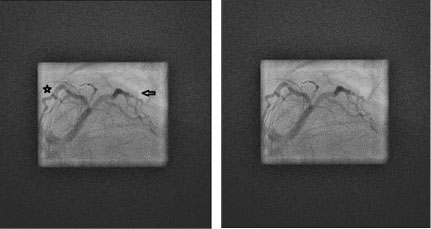

Figure 2: (Labeled and unlabeled).

An elongated left main coronary artery gives rise to the left anterior descending artery (star) which then gives off a substantial bifurcating diagonal branch (arrow) in the left anterior oblique, caudal ("spider") view via cinematography during the left heart catheterization. View Figure 2

Figure 3: (Labeled and unlabeled).

This is an 8x magnification of the left anterior oblique, caudal ("spider") view via cinematography during the left heart catheterization, showing the left anterior descending artery (star) and large diagonal branch (arrow) but there is also no sign of a left circumflex stump or cleft that may suggest an occluded left circumflex branch. View Figure 3

Congenital anomalies of the coronary vasculature are usually asymptomatic and rare with an incidence of less than 1% [1]. Complete absence of the left circumflex is an extremely rare finding with reported incidence of only 0.003% [2]. There are few cases reported of congenital absence of the left circumflex artery but in each case there is an elongated left main coronary artery (Figure 1), substantial diagonal branches from the left anterior descending artery (Figure 2 and Figure 3), and a super-dominate right coronary artery (Figure 4) to perfuse the lateral wall. It is important to recognize this anomaly and define the anatomy by left heart catheterization or coronary angiography by computerized tomography when considering percutaneous intervention or coronary artery bypass surgery on patients without a left circumflex artery [3].